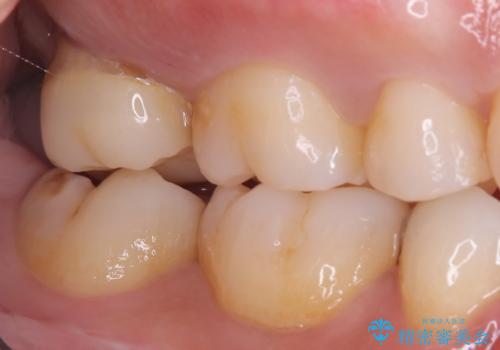

- 海外に転居する前に治療を完了させたいと来院された患者様です。

根管治療からセラミッククラウンまで来院回数は5回で治療を完了することができました。

治療前は遠心のポケットが7mmほどありましたが、治療後には3mmに改善しています。